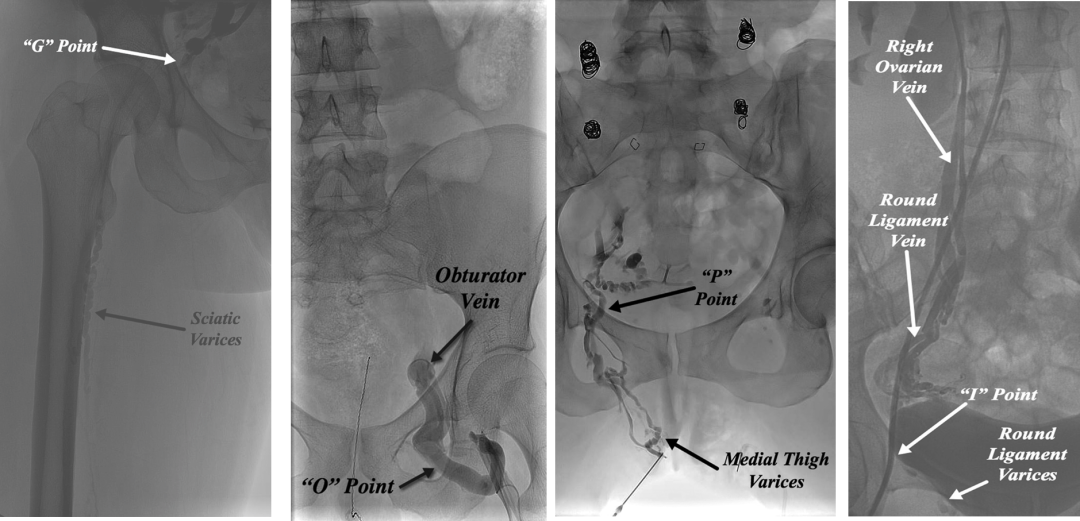

盆腔高压血液通过特定通道“逃逸”至体表,形成非典型静脉曲张:

I 点(Inguinal point):腹股沟管 → 腹壁/大腿根部曲张;

O 点(Obturator point):闭孔静脉 → 大腿内侧疼痛/曲张;

P 点(Perineal point):会阴静脉 → 会阴部曲张;

G 点(Gluteal point):臀下静脉 → 臀肌疼痛、坐骨区曲张。